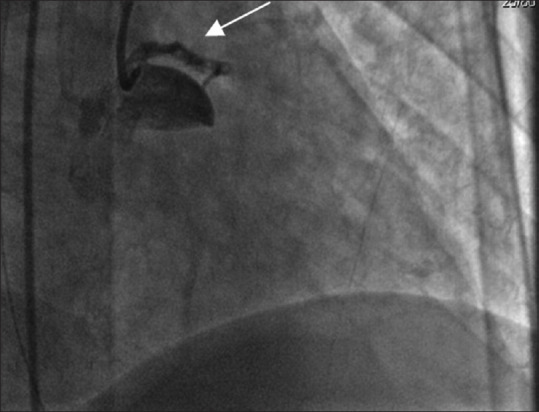

Spontaneous coronary artery dissection is becoming an important cause of acute coronary syndrome, particularly among young women. Its association with female gender, pregnancy, and postpartum period and emotional stress differentiate it from atherosclerotic heart disease. In recent years, there has been more awareness and improved diagnostic and management capabilities, which in turn has increased the diagnostic yield, although knowledge gaps remain. In the present case, a 36-year-old female, who was at 1-month postpartum period, presented with ventricular fibrillation and cardiac arrest. The clinical course was associated with pulmonary hemorrhage. The patient had no current atherosclerotic risk factors, only a family history of sudden cardiac arrest in her mother and sister. She underwent a coronary angiogram, which revealed spontaneous coronary artery dissection (SCAD) in both the left anterior descending and left circumflex artery. Percutaneous coronary intervention was performed but the clinical course was associated with pulmonary hemorrhage. Bronchopulmonary lavage was performed as a diagnostic and therapeutic intervention, and she was discharged in good health. SCAD is an important differential diagnosis in young females presenting with acute coronary syndrome or cardiac arrest. Early recognition and diagnosis are important to decrease the high mortality rate of this disease.